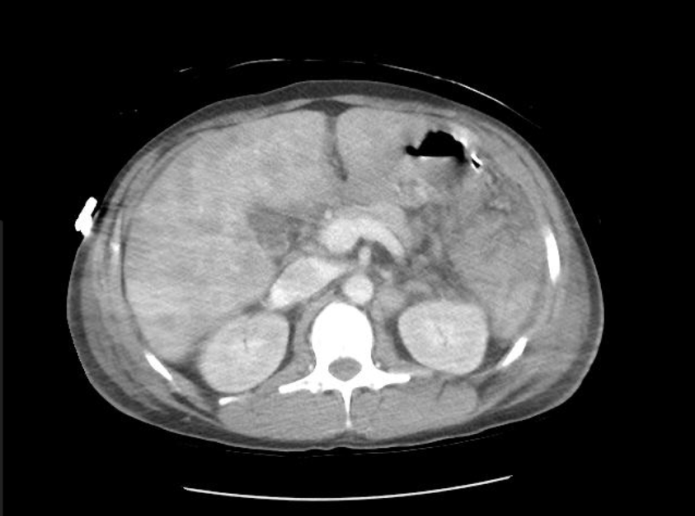

Abstract: We report a case of a 34 year old male with AIDS who presented to the hospital with abdominal pain and dyspnea. He received a comprehensive work-up including extensive imaging and biopsies revealing high grade mature B-cell lymphoma with features consistent with Burkitt’s Lymphoma with concomitant Ebstein Barr viremia. This case demonstrates the need for vigilance when assessing patients with HIV or AIDS for lymphoma with vague complaints and no identifiable source of infection.References